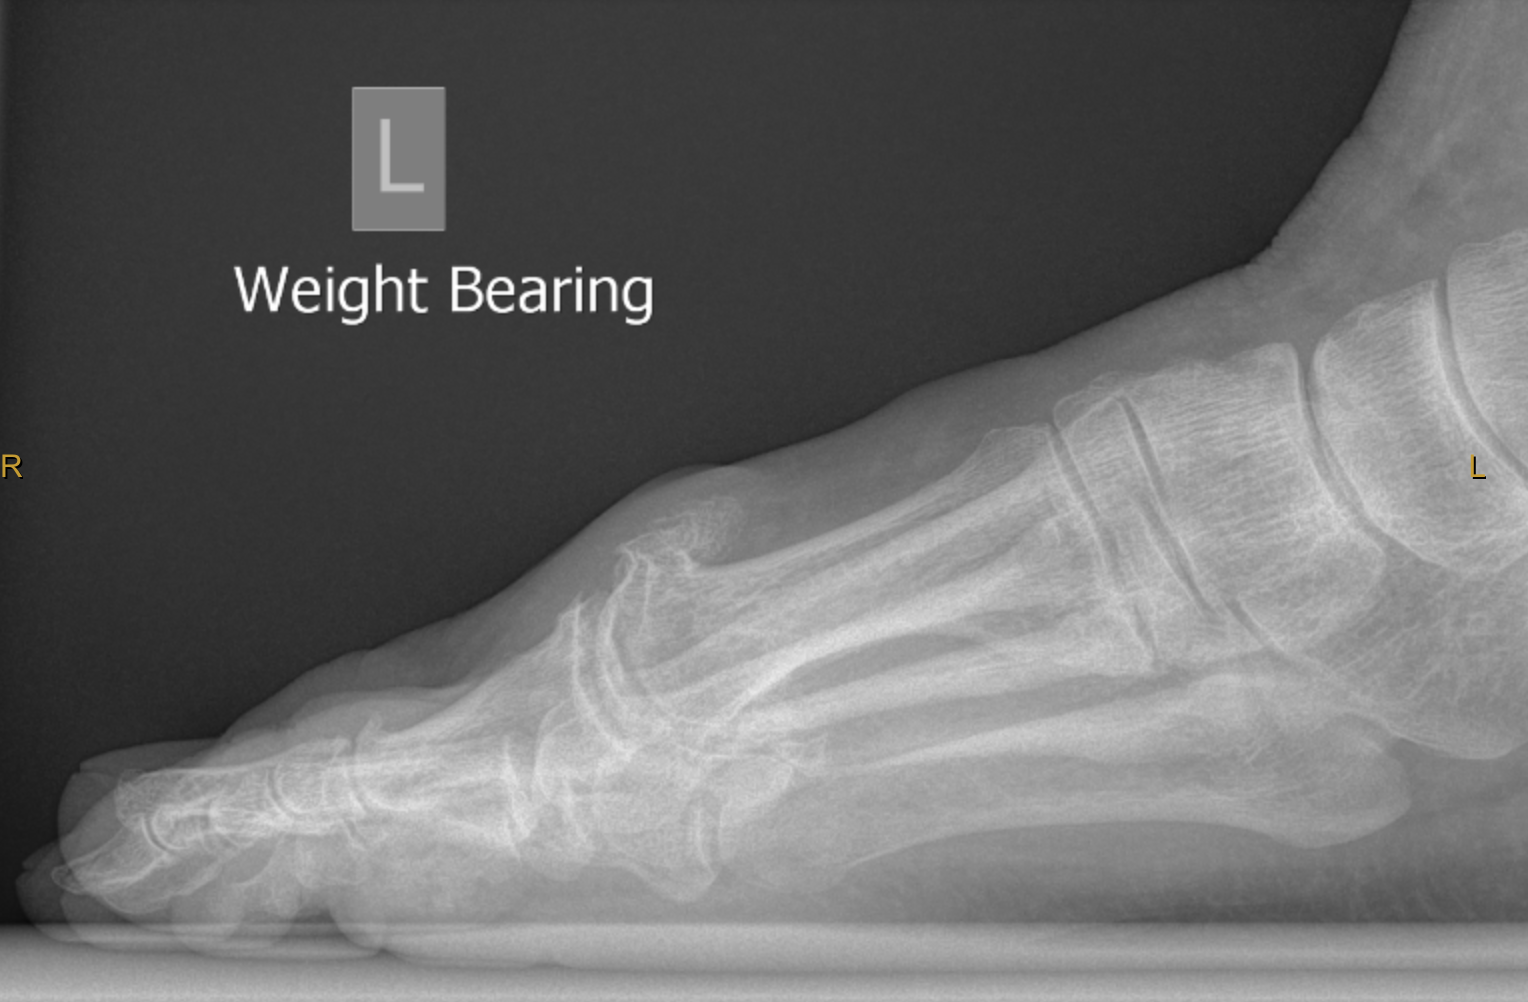

Spur on toe joint sales

Spur on toe joint sales, Physical Therapy in Burr Ridge Hinsdale for Foot Pain Hallux Rigidus sales

Product Name: Spur on toe joint sales

Cheilectomy Big Toe Bone Spur Surgery and Recovery sales, Physical Therapy in Burr Ridge Hinsdale for Foot Pain Hallux Rigidus sales, Cheilectomy Premier Podiatry in Clifton NJ sales, Does Your Big Toe Hurt It Could Be Arthritis Hallux Rigidus Eugene Stautberg MD General Orthopedic Surgeon sales, Foot Surgery Bone Spurs Saint Luke s Health System sales, Minimal Incision Toe Bone Spur Removal sales, Spurs Treatment Foot Doctor Southlake Keller Flower Mound North Richland Hills Argyle and Denton TX sales, Arthritic Big Toe Foot First Podiatry Centers sales, Big Toe Arthritis Footcare Friday Alpine Orthopedics and Sports Medicine Orthopedic Surgery sales, Bone Spur Osteophyte Causes Symptoms Treatment sales, Cheilectomy 2022 Top Foot Doctor Podiatrist in NYC sales, Hallux Rigidus Stiff Big Toe OrthoInfo AAOS sales, Hallux Rigidus Stiff Big Toe OrthoInfo AAOS sales, Big Toe Arthritis Surgery Dr. Blitz Big Toe Arthritis Surgery in NYC Beverly Hills Dr Neal Blitz sales, Blackmer Foot Ankle Hallux Rigidus Big Toe Joint Arthritis in Meridian sales, Bone Spur Treatment Symptoms and Prevention Preferred Foot Ankle sales, Physical Therapy in Burr Ridge Hinsdale for Foot Pain Hallux Rigidus sales, Hallux Rigidus Stiff Big Toe OrthoInfo AAOS sales, Big Toe Pain Dr Mike Smith Orthopaedic Surgeon Adelaide sales, Minimally Invasive Correction of Big Toe Arthritis Hallux Rigidus CNOS sales, Hallux Rigidus Arthritis of the big toe Christopher Miller sales, Big Toe Pain Dr Mike Smith Orthopaedic Surgeon Adelaide sales, Treatment for Arthritic Big Toe Joints Hallux Rigidus Perth Foot Centre sales, Big Toe Joint Pain Treatment Sydney Big Toe Joint Pain Treatment Sydney sales, Arthritis of the Big Toe Hallux Rigidus What Are My Treatment Options OrthoVirginia sales, Bone Spurs Clinton Twp Macomb MI See a Top Podiatrist Today sales, Heel or Toe Spurs Premier Podiatry Velimir Petkov DPM Podiatrists Clifton NJ sales, Minimally Invasive Correction of Big Toe Arthritis Hallux Rigidus CNOS sales, Bone Spur On Top Of The Foot Learn the causes and treatment sales, Hallux Rigidus Big Toe Arthritis FootEducation sales, Arthritis of the Big Toe Hallux Rigidus What Are My Treatment Options OrthoVirginia sales, Big Toe Arthritis Hallux Rigidus Symptoms Causes sales, Bone Spur On Top Of The Foot Learn the causes and treatment sales, Bone spurs Causes symptoms and treatment in Scottsdale Arizona Foot Doctors sales, Big Toe Joint Conditions Ottawa Foot Clinic sales.

Cheilectomy Big Toe Bone Spur Surgery and Recovery sales, Physical Therapy in Burr Ridge Hinsdale for Foot Pain Hallux Rigidus sales, Cheilectomy Premier Podiatry in Clifton NJ sales, Does Your Big Toe Hurt It Could Be Arthritis Hallux Rigidus Eugene Stautberg MD General Orthopedic Surgeon sales, Foot Surgery Bone Spurs Saint Luke s Health System sales, Minimal Incision Toe Bone Spur Removal sales, Spurs Treatment Foot Doctor Southlake Keller Flower Mound North Richland Hills Argyle and Denton TX sales, Arthritic Big Toe Foot First Podiatry Centers sales, Big Toe Arthritis Footcare Friday Alpine Orthopedics and Sports Medicine Orthopedic Surgery sales, Bone Spur Osteophyte Causes Symptoms Treatment sales, Cheilectomy 2022 Top Foot Doctor Podiatrist in NYC sales, Hallux Rigidus Stiff Big Toe OrthoInfo AAOS sales, Hallux Rigidus Stiff Big Toe OrthoInfo AAOS sales, Big Toe Arthritis Surgery Dr. Blitz Big Toe Arthritis Surgery in NYC Beverly Hills Dr Neal Blitz sales, Blackmer Foot Ankle Hallux Rigidus Big Toe Joint Arthritis in Meridian sales, Bone Spur Treatment Symptoms and Prevention Preferred Foot Ankle sales, Physical Therapy in Burr Ridge Hinsdale for Foot Pain Hallux Rigidus sales, Hallux Rigidus Stiff Big Toe OrthoInfo AAOS sales, Big Toe Pain Dr Mike Smith Orthopaedic Surgeon Adelaide sales, Minimally Invasive Correction of Big Toe Arthritis Hallux Rigidus CNOS sales, Hallux Rigidus Arthritis of the big toe Christopher Miller sales, Big Toe Pain Dr Mike Smith Orthopaedic Surgeon Adelaide sales, Treatment for Arthritic Big Toe Joints Hallux Rigidus Perth Foot Centre sales, Big Toe Joint Pain Treatment Sydney Big Toe Joint Pain Treatment Sydney sales, Arthritis of the Big Toe Hallux Rigidus What Are My Treatment Options OrthoVirginia sales, Bone Spurs Clinton Twp Macomb MI See a Top Podiatrist Today sales, Heel or Toe Spurs Premier Podiatry Velimir Petkov DPM Podiatrists Clifton NJ sales, Minimally Invasive Correction of Big Toe Arthritis Hallux Rigidus CNOS sales, Bone Spur On Top Of The Foot Learn the causes and treatment sales, Hallux Rigidus Big Toe Arthritis FootEducation sales, Arthritis of the Big Toe Hallux Rigidus What Are My Treatment Options OrthoVirginia sales, Big Toe Arthritis Hallux Rigidus Symptoms Causes sales, Bone Spur On Top Of The Foot Learn the causes and treatment sales, Bone spurs Causes symptoms and treatment in Scottsdale Arizona Foot Doctors sales, Big Toe Joint Conditions Ottawa Foot Clinic sales.